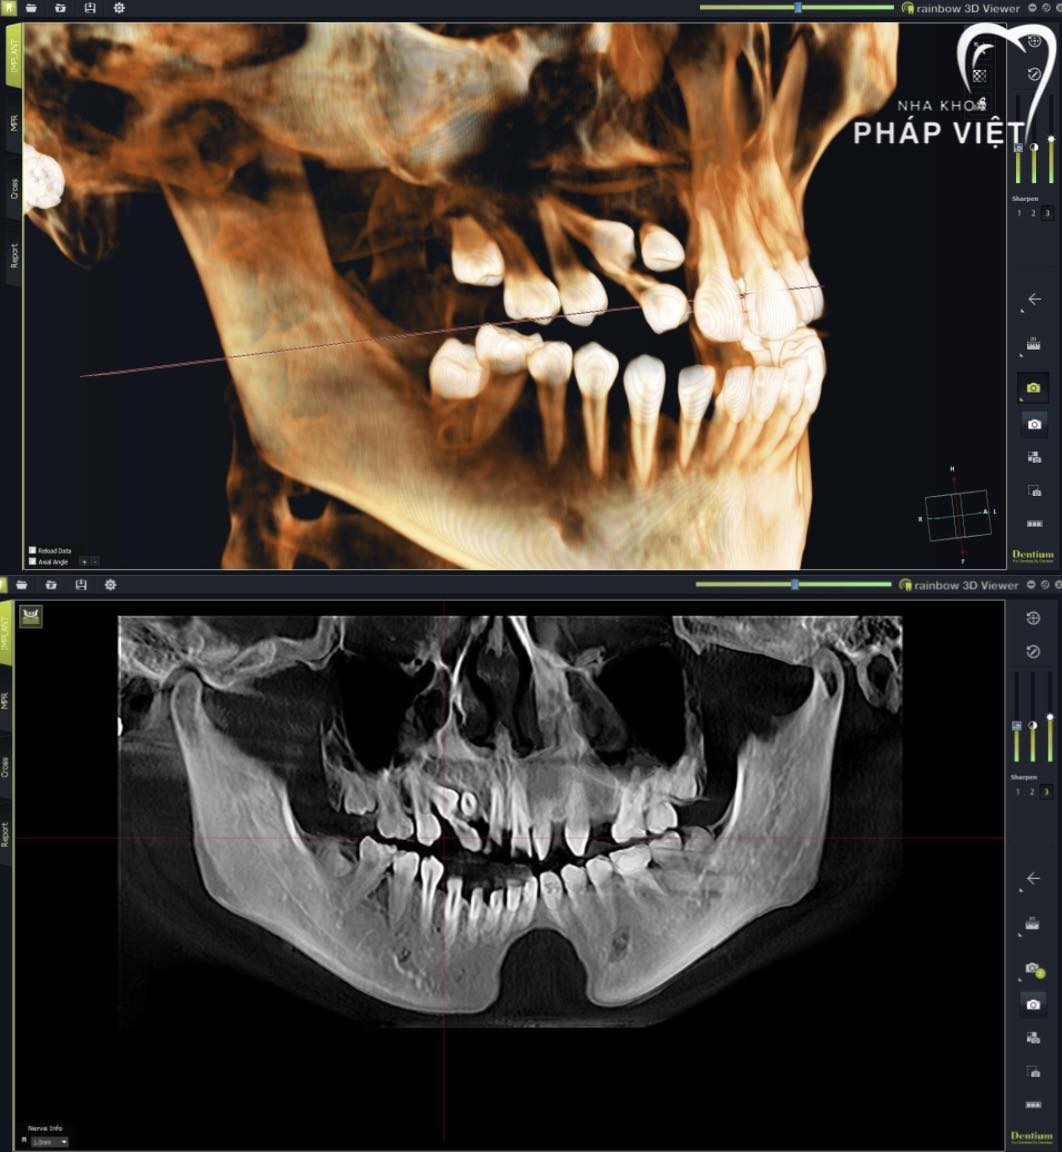

Trung tâm nha khoa thẩm mỹ kỹ thuật cao NHA KHOA PHÁP VIỆT Chuyên cung cấp các dịch vụ nha khoa điều trị, phòng ngừa, và các dịch vụ nha khoa thẩm mỹ phục hình răng sứ cao cấp, chỉnh hình răng hô móm, lệch lạc, cắm ghép implant, tẩy trắng răng kỹ thuật cao… Nha khoa Pháp Việt do đội ngũ bác sỹ Răng Hàm Mặt được đào tạo chính quy và đã qua tu nghiệp ở Pháp trực tiếp khám và điều trị. Đặc biệt, chúng tôi luôn luôn miễn phí: Khám và tư vấn về chăm sóc răng miệng Nhổ răng sữa lung lay dùng thuốc tê bôi.

Nha Khoa Pháp Việt với nhiều năm kinh nghiệm trong lĩnh vực điều trị, phòng ngừa và các dịch vụ nha khoa thẩm mỹ phục hình răng sứ cao cấp, chỉnh hình răng hô móm, lệch lạc, cắm ghép implant, tẩy trắng răng kỹ thuật cao,... Với đội ngũ bác sỹ chuyên nghiệp được đào tạo chuyên sâu giúp mang lại cho mọi người tự tin với hàm răng chắc khỏe.